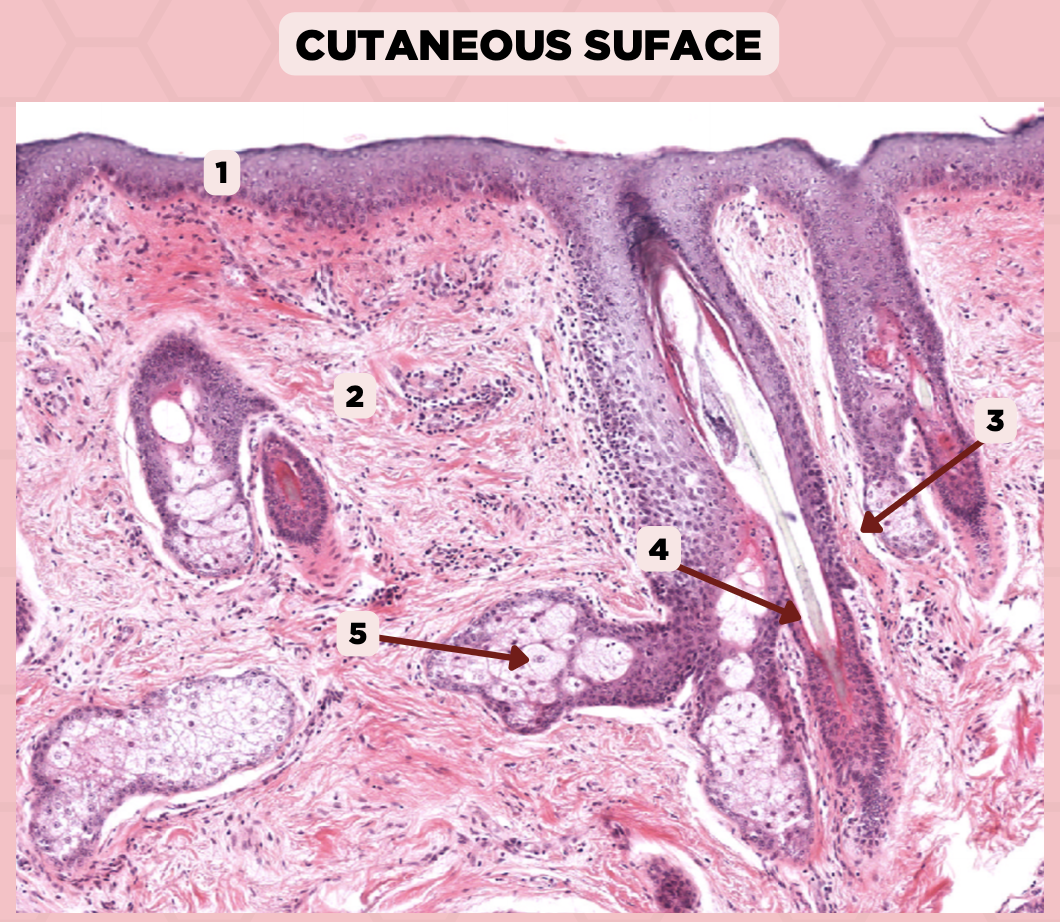

Lip

What is the specimen showed in the picture?

Epidermis

Identify the structure labeled as 1.

Dermis

Identify the structure labeled as 2.

Arrector Pilli Muscle

Identify the structure labeled as 3.

Hair Follicle

Identify the structure labeled as 4.

Sebaceous Glands

Identify the structure labeled as 5.